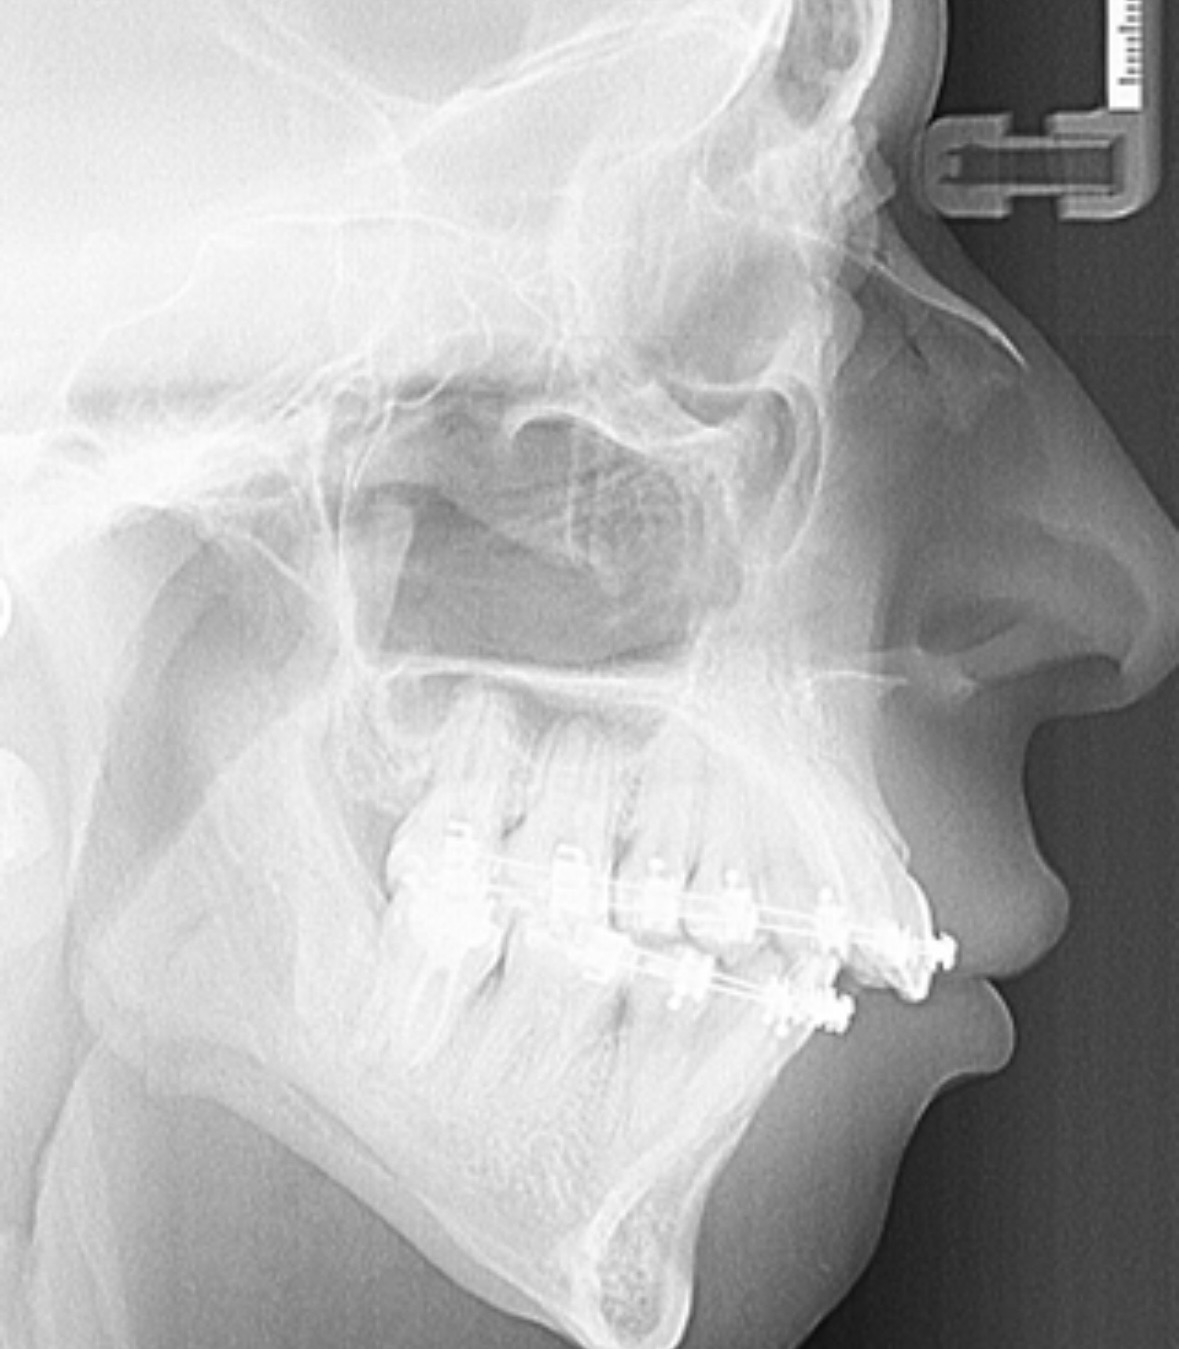

wondering if its because of too much maxilla movements or someting else like ccw

upper incisors forward movementwondering if its because of too much maxilla movements or someting else like ccw

View attachment 4715858 View attachment 4715860

is this the result of the maxilla movement or its a predisposition of the teeth being already like thatupper incisors forward movement